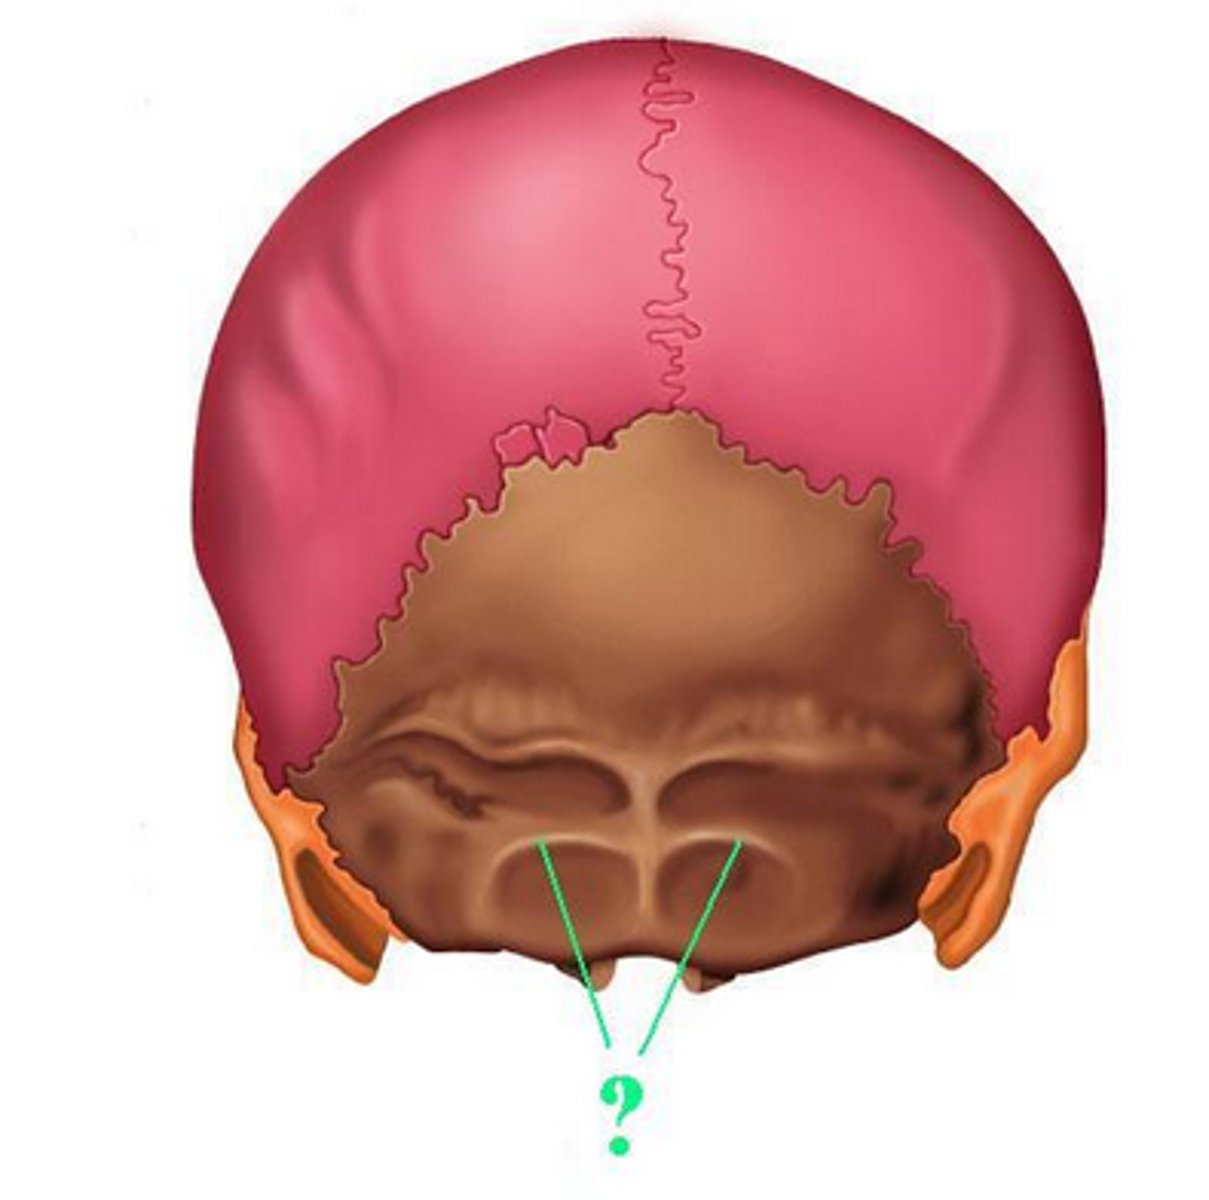

posterior cranial fossa

portion of cranial canal formed by the occipital

occipital condyles of occipital bone

rounded processes that articulate with the atlas (C1)